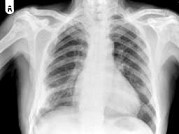

- 单项选择题男,77岁, 全身性骨痛,夜间加重, 贫血,PSA大于100, 结合图像,最可能的诊断是 ( )

A、成骨性骨转移

B、多发性骨髓瘤

C、慢性化脓性骨髓炎

D、骨肉瘤

E、以上都不是